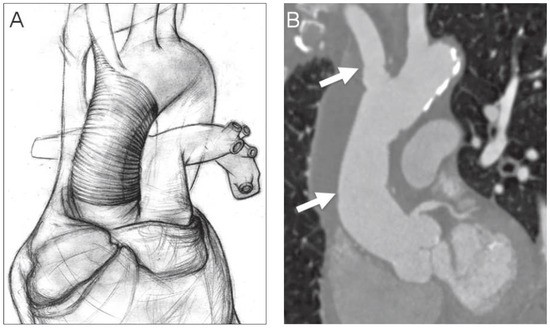

Simple Repair Technique for Rupture of the Brachiocephalic Trunk

by Grzegorz Zuk, Jens Bremerich, Friedrich Eckstein and Peter Matt

Cardiovasc. Med. 2015, 18(2), 68; https://doi.org/10.4414/cvm.2015.00320 - 18 Feb 2015

Abstract

A 79–year-old woman with chronic obstructive pulmonary disease and history of severe arterial hypertension was admitted to our hospital due to recurrent chest discomfort and dyspnea [...] Full article

Show Figures

Figure 1